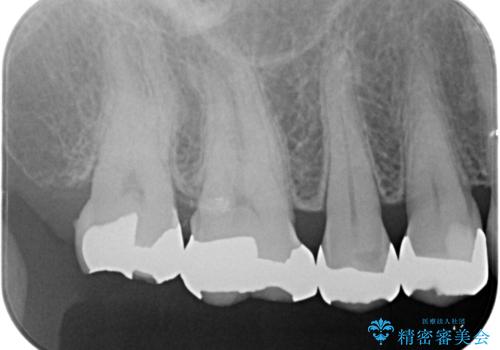

- 詰め物が欠けたとのことで来院されました。

実際は詰め物ではなく歯自体が欠けている状態でした。

銀の詰め物を外し、欠けたところを覆うように新しい詰め物を作成します。

- 右上5 ゴールドアンレー 77,000円費用は治療当時の料金となります

欠けたところに金属を使用することで、再度欠けてしまうリスクを抑えました。